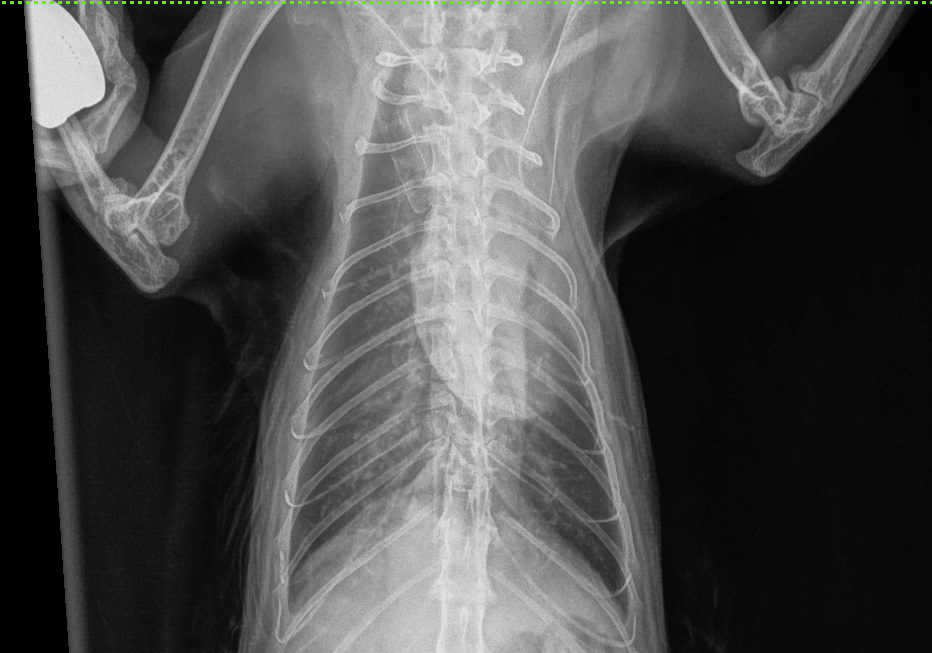

При биохимическом анализе сыворотки крови выявлено незначительное повышение уровней креатинина и мочевины, что согласуется с наличием в анамнезе хронической болезни почек у данного пациента (табл. 1). Клинический анализ крови демонстрирует выраженные изменения в составе эритроцитов (красных кровяных телец), что может свидетельствовать о развитии у пациента регенераторной анемии (табл.2), поскольку количество ретикулоцитов у него находится в пределах нормы (табл. 3). В свою очередь анемия как паранеопластический синдром отмечается у 43–58% кошек с лимфомой и у 30–43% собак. Она является неблагоприятным прогностическим фактором для обоих видов животных32-34.Рентгенография. После проведения рентгенографии грудной клетки в вентродорсальной и латеролатеральной проекциях выявлены следующие изменения: затемнение в области краниальных долей легких, сглаженность тени сердца. На рентгенограммах также обнаружены затемнения в каудальных долях легких, соответствующие ателектазу и смещению вентральной границы между вентральной стенкой грудной клетки, что может указывать на развитие гидроторакса в умеренном количестве (рис. 1, 2)